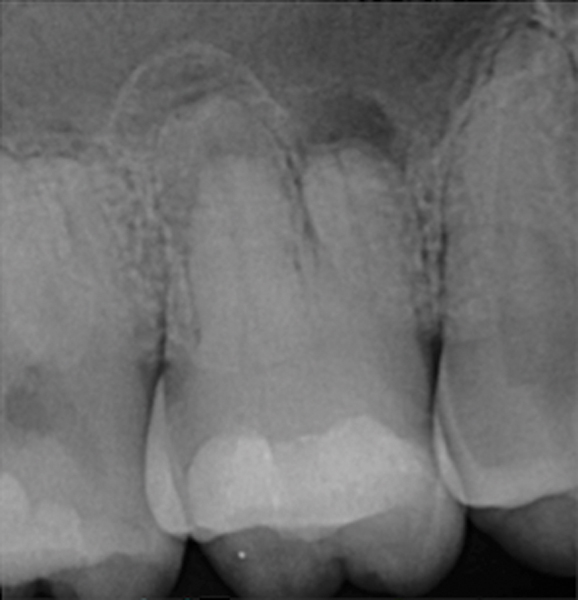

Fig 6. Preoperative radiograph of carious exposure on tooth No. 19. Courtesy of Dr. Mohammed A. Alharbi.

Figure 6